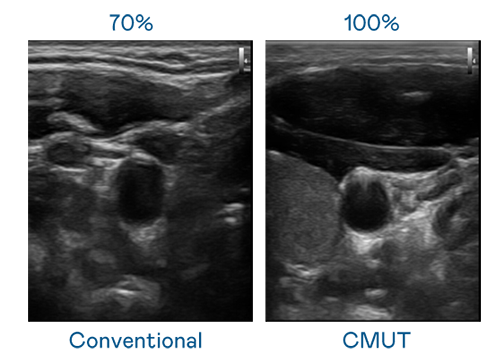

CMUT 技术是一种用电容式微机电元件来产生超音波讯号的技术。与传统 PZT 压电式技术相比,CMUT 频宽增加 30%,更宽频的超音波讯号让影像解析度大幅提升,是实现高影像品质医疗超音波扫描、促进精准医疗发展的关键技术。

超音波影像的解析度高低,首先取决于探头能发出的讯号频宽。征途国际 CMUT 可提供高清晰的超音波讯号,提供高频宽、高灵敏度、影像纹理细节更高的超音波影像,协助医护人员缩短影像判读时间及利用精准的医疗影像进行诊断。